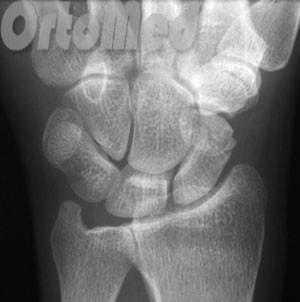

Перелом ладьевидной кости

Причиной травмы становится падение на согнутую кисть, удар сжатой в кулак кистью по твердому предмету или прямой удар по ладони. Как правило, ладьевидная кость ломается на два фрагмента. Возможно внутри- и внесуставное повреждение. К внесуставным переломам относится отрыв бугорка ладьевидной кости. Перелом ладьевидной кости может сочетаться с вывихом полулунной кости (переломовывих де Кервена).

Ладьевидная кость является одной из мелких костей запястья. Из всех костей в запястья, переломы ладьевидной кости являются наиболее распространенными. Ладьевидная кость - небольшая кость запястья на стороне большого пальца (с лучевой стороны).

Запястье состоит из восьми мелких костей, известных как кости запястья. Кости запястья образуют два ряда по четыре кости в каждом, которые располагаются между пястными костями и костями предплечья (лучевой и локтевой). Ладьевидную кость можно пропальпировать в области "анатомической табакерки». Эта точка расположена между сухожилиями длинного разгибателя большого пальца и длинной отводящей мышцы.

Первым и обязательным диагностическим моментом является рентгенография поврежденного участка конечности. Чаще всего рентгенография ясно показывает характер перелома ладьевидной кости.

Если перелом ладьевидной кости происходит без смещения отломков, то линию перелома на рентгенограмме можно и не увидеть. Поэтому очень важно при любой травме кисти выполнить шинирование на 10 дней. На 10 день повторить рентгенограммы кисти и, если перелом все же был, он станет четко просматриваться. Ну а далее выполняют соответствующие лечебные мероприятия (см. раздел лечение переломов ладьевидной кости).